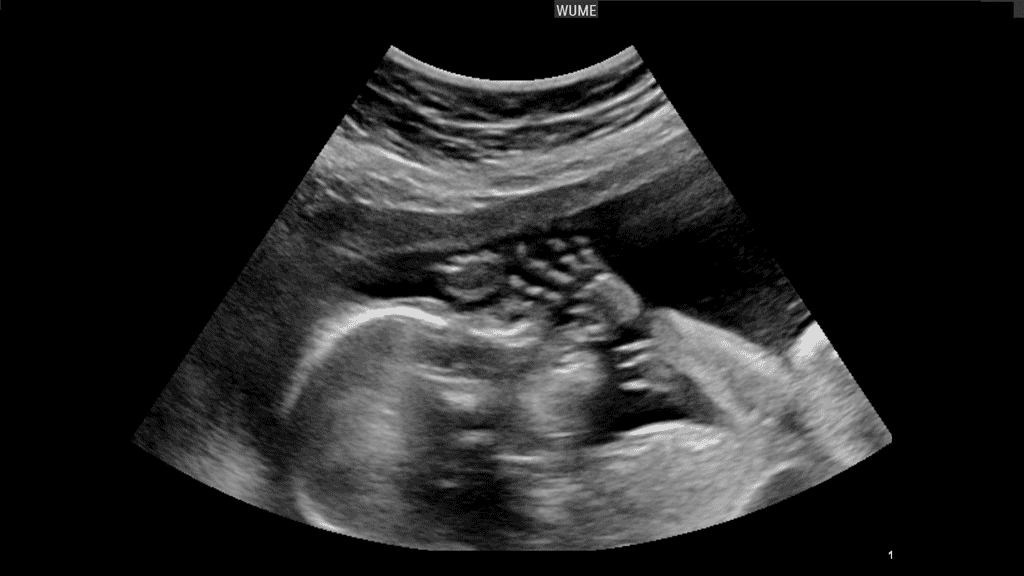

سونوگرافی آنومالی یکی از مهمترین و حساسترین آزمایشهای دوران بارداری است که به طور معمول بین هفتههای ۱۸ تا ۲۲ بارداری انجام میشود. این نوع سونوگرافی به پزشکان کمک میکند تا ناهنجاریها یا مشکلات احتمالی جنین را شناسایی کرده و سلامت کلی او را ارزیابی کنند. دقت در انتخاب مرکز سونوگرافی آنومالی بسیار اهمیت دارد، زیرا این آزمایش نقش تعیینکنندهای در مدیریت بارداری و برنامهریزی برای مراقبتهای پزشکی دارد.

سونوگرافی آنومالی برای بررسی رشد و تکامل صحیح اندامهای جنین انجام میشود. در این آزمایش، پزشک ساختار اندامهای حیاتی مانند قلب، مغز، کلیهها، ستون فقرات، صورت و اندامهای حرکتی جنین را بررسی میکند. یک مرکز تخصصی با تجهیزات پیشرفته و کادر مجرب میتواند ناهنجاریهای احتمالی مانند نقص لوله عصبی، مشکلات قلبی یا اختلالات اسکلتی را با دقت بیشتری تشخیص دهد. این تشخیصها بسیار حساس هستند و خطا در آنها میتواند پیامدهای جدی برای مادر و جنین داشته باشد.

رشد متناسب جنین یکی از معیارهای اصلی سلامت اوست. در سونوگرافی آنومالی، پزشک اندازهگیریهای دقیقی از قسمتهای مختلف بدن جنین مانند دور سر، دور شکم و طول استخوان ران انجام میدهد. این اندازهگیریها باید با استانداردهای رشد جنین تطبیق داده شوند. مراکز تخصصی که از دستگاههای پیشرفته استفاده میکنند، میتوانند تصاویر و اندازهگیریهای دقیقتری ارائه دهند، که این امر برای ارزیابی رشد و تشخیص تأخیرهای احتمالی اهمیت زیادی دارد.